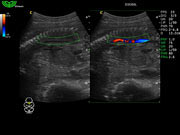

Многократное составное отображение (MCI)

Как в бестеневой лампе, ультразвуковая волна передается под разными углами для предоставления врачу большего количества информации и получения более качественных изображений.

В этом специальном режиме сканирования B датчик передает звуковые волны не только перпендикулярно, а также и в других плоскостях, вращая направление распространения волн. Затем эти плоскости перекрываются и формируют конечное изображение. Это улучшает пространственное и контрастное разрешение и уменьшает отражения на границе.

- Увеличивает линейную плотность, улучшает качество изображения.

- Улучшает контрастное разрешение; позволяет более четко различать слои тканей и края сосудов.

- Уменьшает поперечный эффект на границах тканей, что делает органы более различимыми.

- Уменьшает тени, создаваемые звуковой волной.